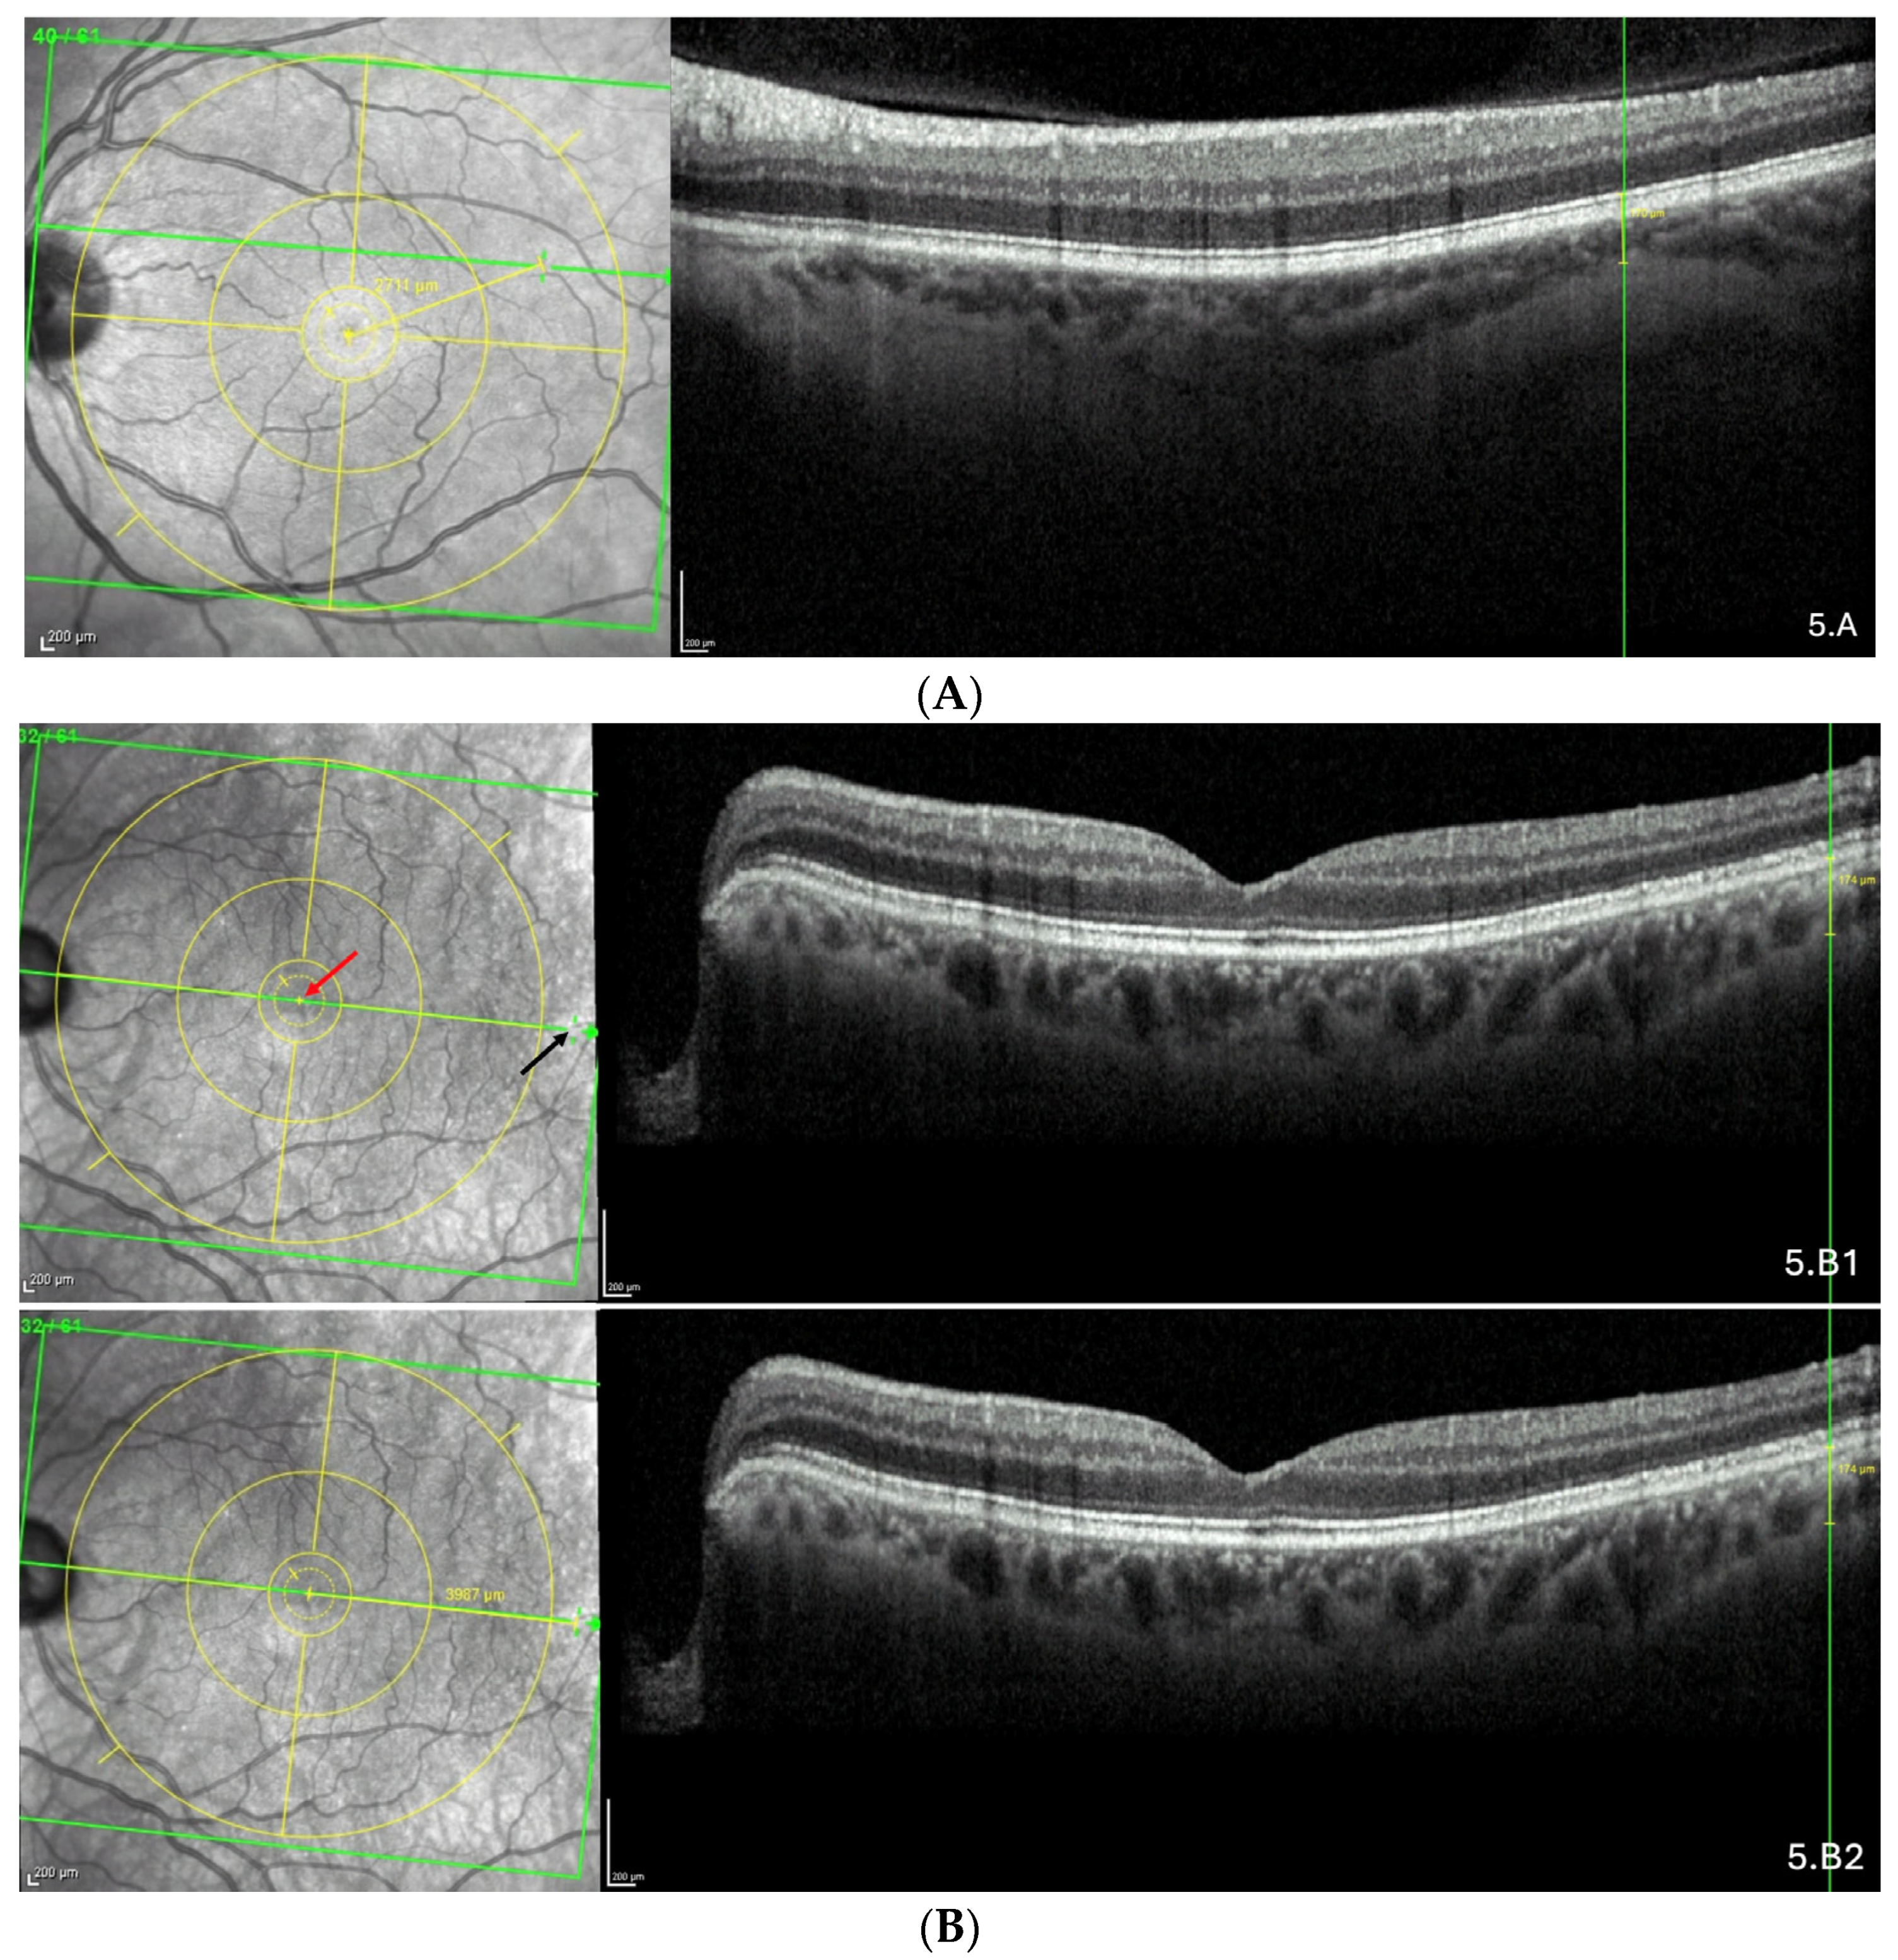

3.4. Detailed Analysis of Choroidal Thinning at the Vicinity of the Fo-BMO Axis (ChT)

| Location | Sample Size (n) | Present (n) | Proportion % |

|---|---|---|---|

| Upper part of rectangle | 109 | 25 | 22.9 |

| Part centered by the Fo-BMO axis | 112 | 78 | 69.6 |

| Lower part of rectangle | 114 | 29 | 25.4 |

| Location | Sample (n) | % | Mean Thickness | SEM | Range |

|---|---|---|---|---|---|

| Superior location | 23 | 29.5 | 130.1 | 11.6 | 19.5–248.0 |

| Along the Fo-BMO axis | 22 | 28.2 | 93.7 | 12.7 | 9.0–254.0 |

| Inferior location | 33 | 42.3 | 101.7 | 10.7 | 10.0–248.0 |

| Total | 78 | 100.0 | 107.8 | 6.9 | 9.0–248.0 |